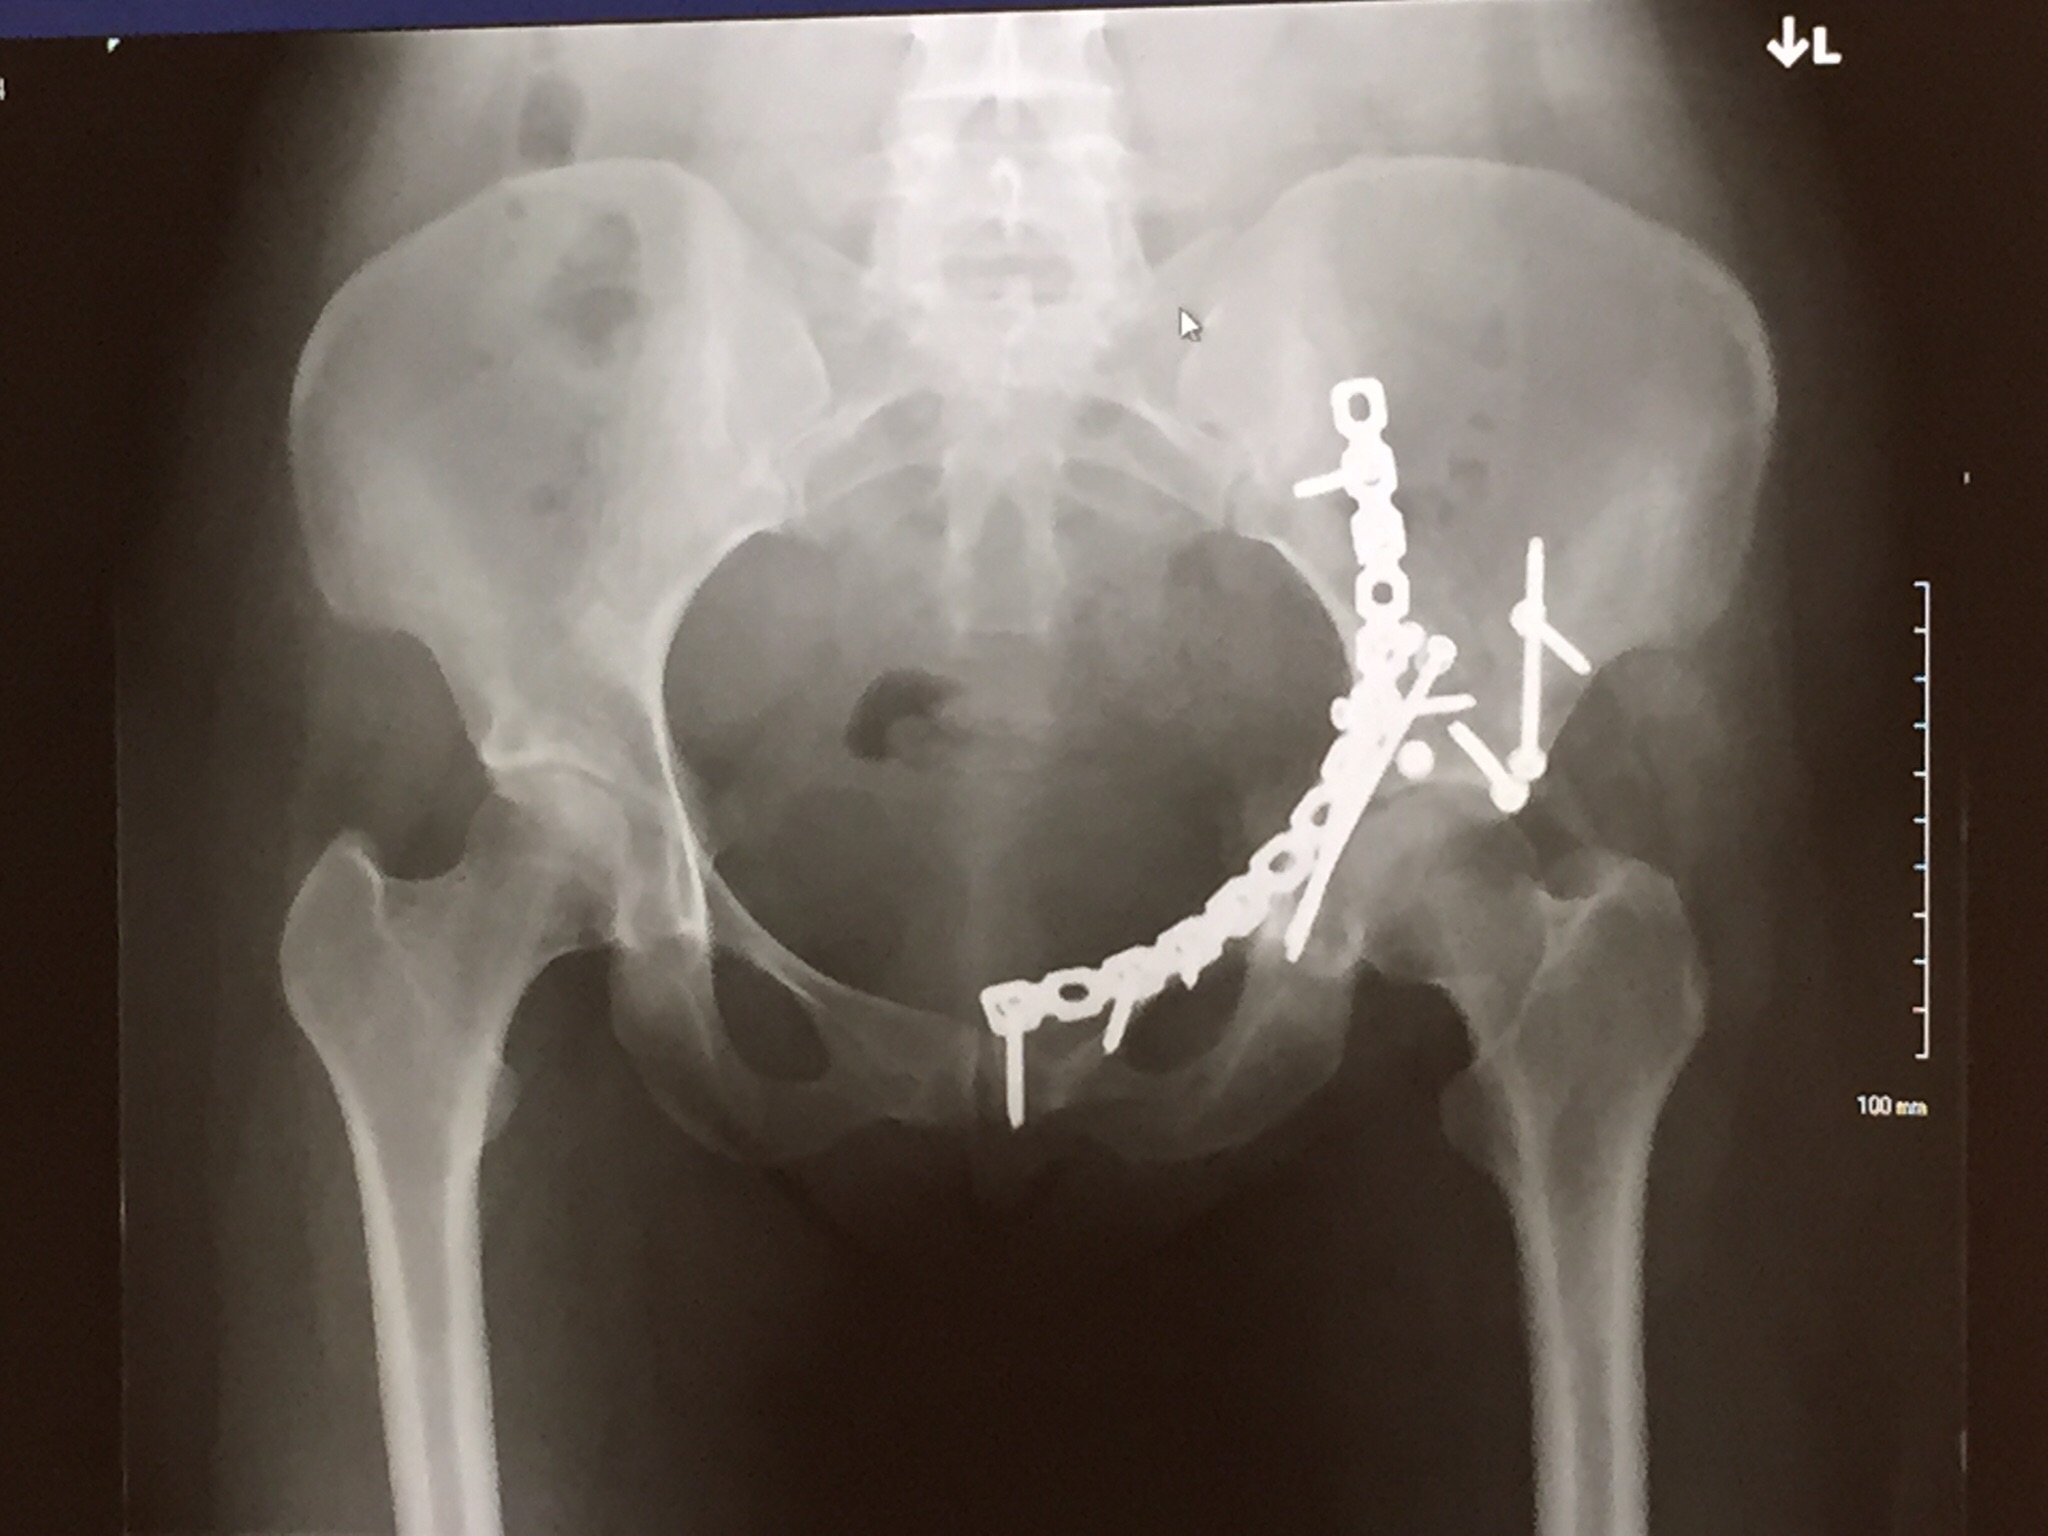

I was recovering after my seven hour surgery in the Orthopedic Trauma ICU. I had shattered my hip and the very talented orthopedic trauma surgeons fixed the “pretzel” with Titanium plates and screws. The nurse gave me a magic button to press every 8 minutes to kill the pain. Morphine. I was hopped up and barely conscious. After my surgery on the 4th of May, the priority was to get me up and awake. Up and awake to get myself beside Jitish to spend as much time as I could with him. The urgency was driven by the lack of knowing how long Jitish had. I saw my sister in bursts and spurts, seeing her rushing in and out, or praying. I didn’t know how bad it was for Jitish. On the 6th of May, the nurses and therapists tried to get me up on the side of the bed. Moments of chaos and panic later, I was back on bed. Morphine. Blood. Sleep. I was told later that the hematoma on my leg had burst. My sister also showed me the x-ray post surgery.